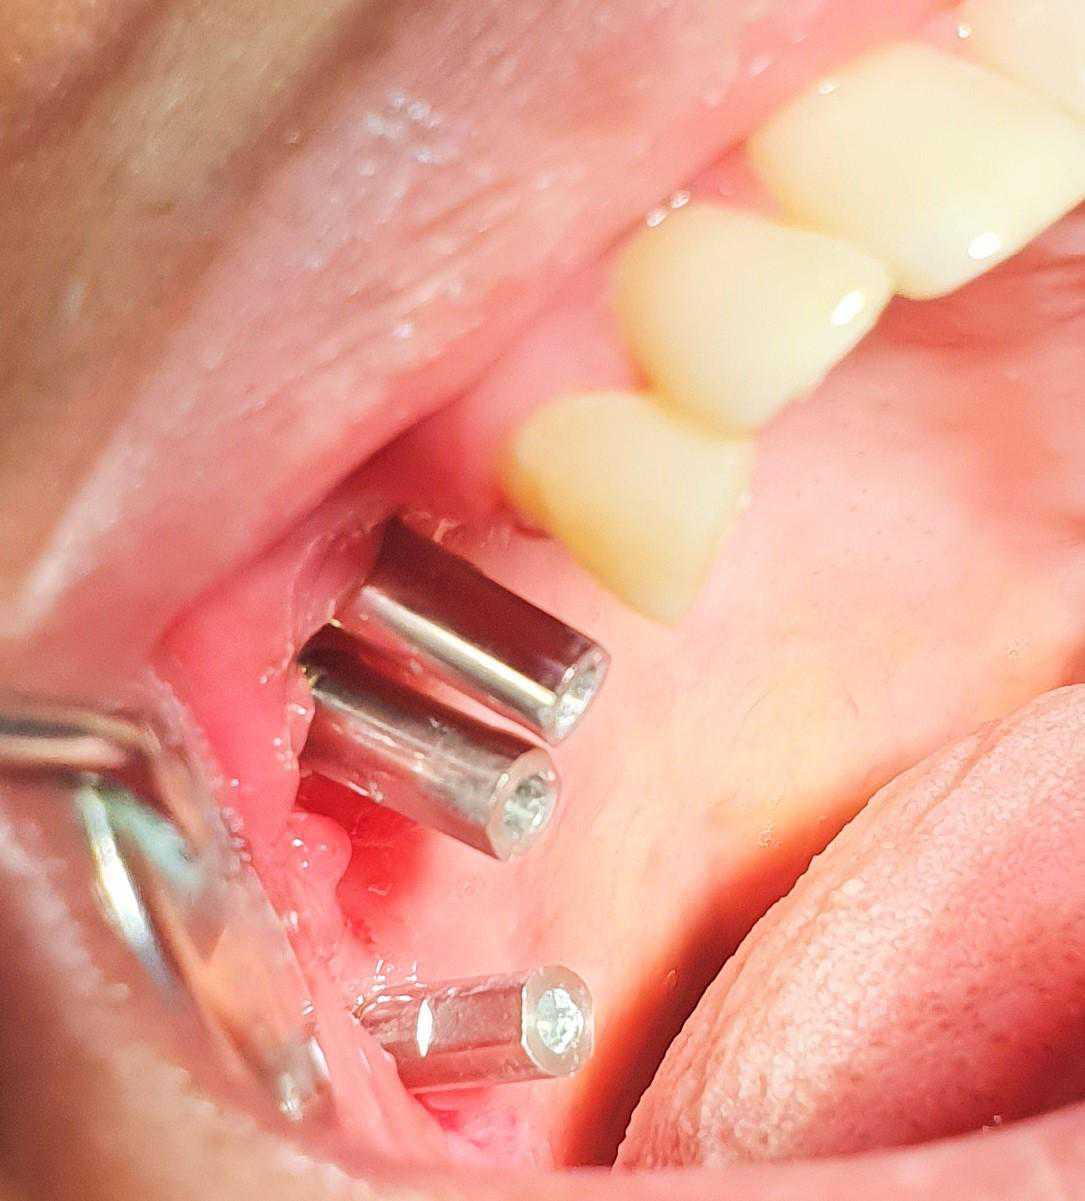

https://demo.discussdentistry.com/forums/topic/post-mucormycosis-avascular-necrosis-of-maxilla-rehabilitation-with-zygomatic/#post-24499 <![CDATA[Post Mucormycosis Avascular necrosis of maxilla, rehabilitation with Zygomatic]]> https://demo.discussdentistry.com/forums/topic/post-mucormycosis-avascular-necrosis-of-maxilla-rehabilitation-with-zygomatic/#post-24499 Thu, 25 Aug 2022 12:14:40 +0000 Sankalp Mittal

• 20210604_101325 (2)20210604_101317 (2)20210604_103315 (2)20210604_102857 (2)20210604_104202 (2)20210604_104853 (2)20210824_105656 (2)20210824_112353 (2)20210824_114957 (2)20210824_131302 (2)20210826_100648 (2)20210826_100749 (2)20210826_100919 (2)20210914_183943 (2)20211001_17535220211012_18543620211012_192043 (2)20211012_185627 (2)20211012_195430 (3)20211027_193725 (2)20211027_200729 (2)20211027_200919